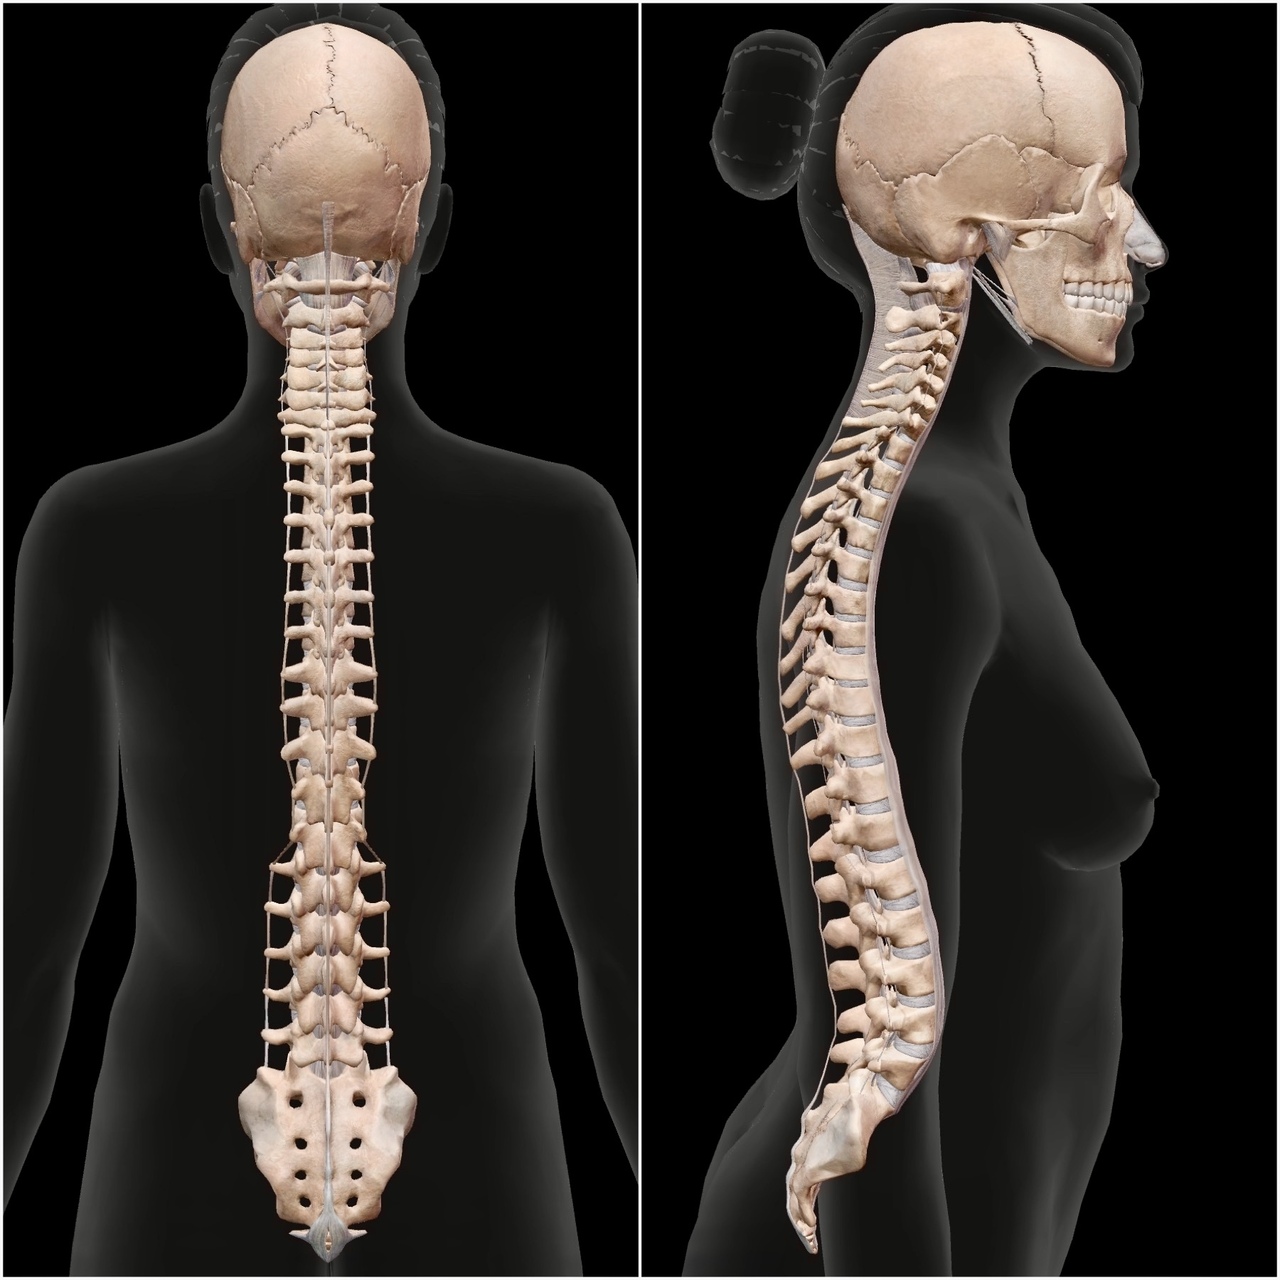

9割は知らない!背骨の役割!ーがじゅまる鍼灸整骨院

背骨の役割ってご存知ですか?

1.筋肉や内臓を支える

重要な筋肉や内臓が支えられ、身体の安定性を保ちます!

2.姿勢の維持

背骨が直立していることによって、姿勢を維持することができます!

簡単にはなりましたが、皆さまが気にされている症状の改善には背骨の関係が必要不可欠です。

背骨の動きが硬くなると肩や腰に負担のかかりやすい姿勢が出来上がり、猫背・肩こり・腰痛などの症状が出てきます!